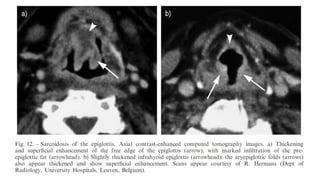

Alveolar Sarcoidosis. In this case the appearance resembles a ground glass

attenuation, but with a close look you may appreciate that the increased attenuation is

the result of many tiny grouped nodules.

Also notice the hilar lymphadenopathy.

The differential diagnosis now includes tumor (bronchoalveolar carcinoma or

lymphoma), eosinophilic pneumonia , organizing pneumonia, Wegener's disease or

an uncommon presentation of sarcoidosis.

There is only one clue to the diagnosis and that is the presence of

small nodules